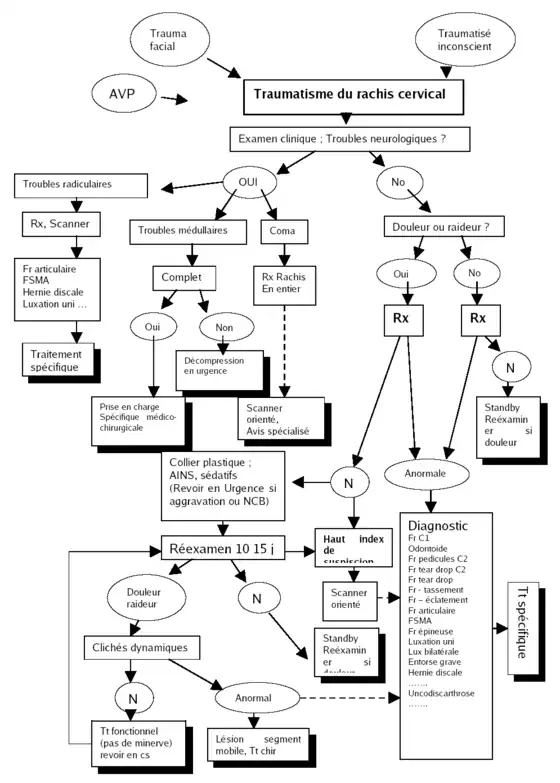

Algorithme de prise en charge